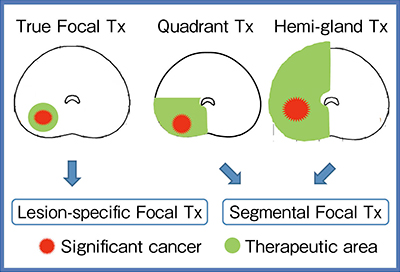

2.標的部位設定

Focal therapyにおける標的部位の設定方法には,True Focal therapyと言われる病巣治療法(Lesion-specific Focal therapy)と,Quadrant therapyあるいはHemi-gland therapyと言われる区域治療法(Segment Focal therapy)がある(図2)。病巣治療法は理想的な方法ではあるが,実際には病巣のマージンやターゲットとなる病巣の特定が困難で非可視病巣は治療できず,過小治療となるリスクがある。一方,区域治療法は治療不要な領域の同定が必要であるが,治療区域設定は比較的容易で,非可視病巣もある程度治療対象とすることができる。正常域が含まれるため過剰治療のリスクはあるが,過小治療のリスクは低減することから,当院では区域治療法を施行している。

図2 Focal therapyの標的部位設定

*TX:therapy